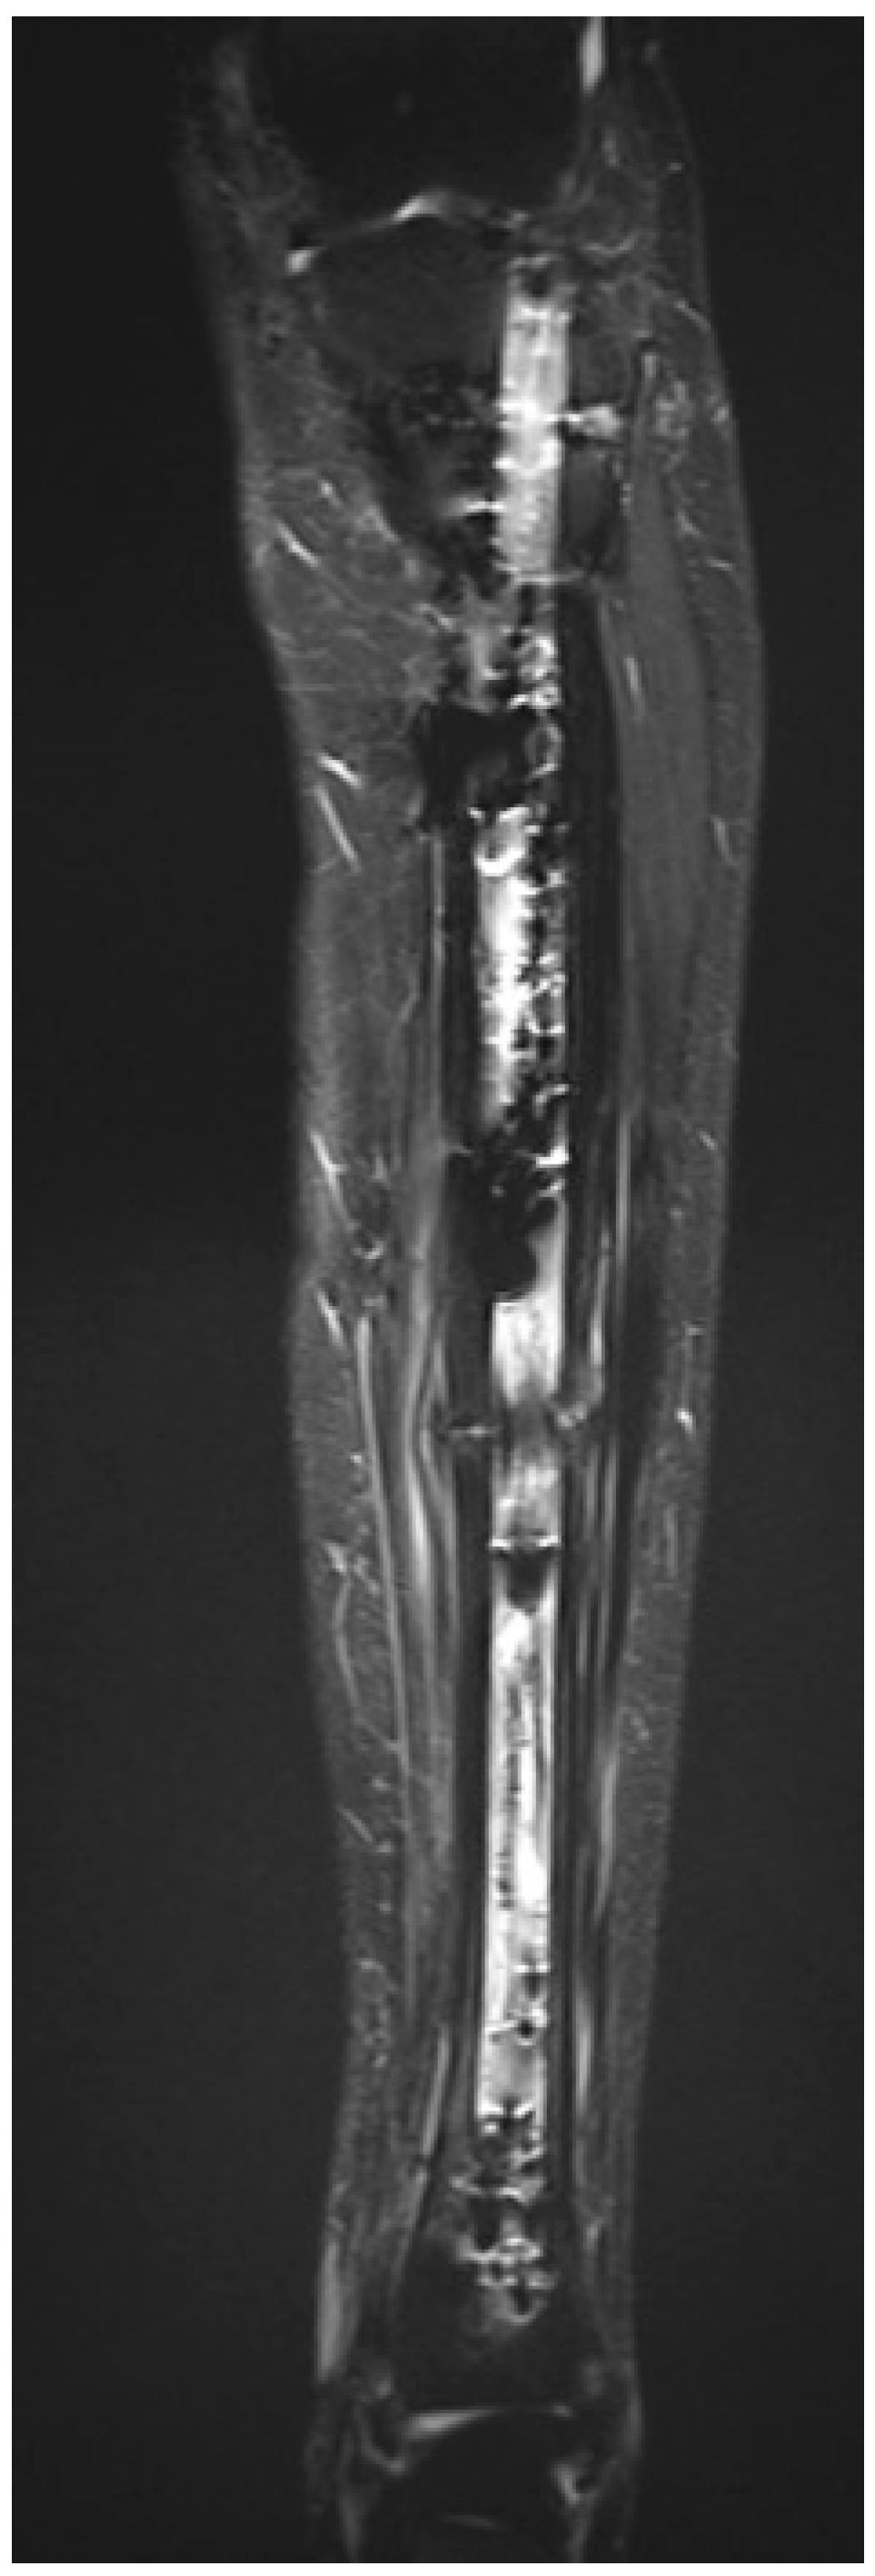

Figure 2.

Preoperative MRI of the left tibial diaphysis demonstrating an OFD/LA. (A) Hypointense lesion on T1-weighted sequence, coronal plane. (B) Hyperintense lesion on T2-weighted fat-suppressed sequence, coronal plane. (C) Hypointense lesion on T1-weighted sequence, axial plane. (D) Hypointense lesion on T2-weighted sequence, axial plane.